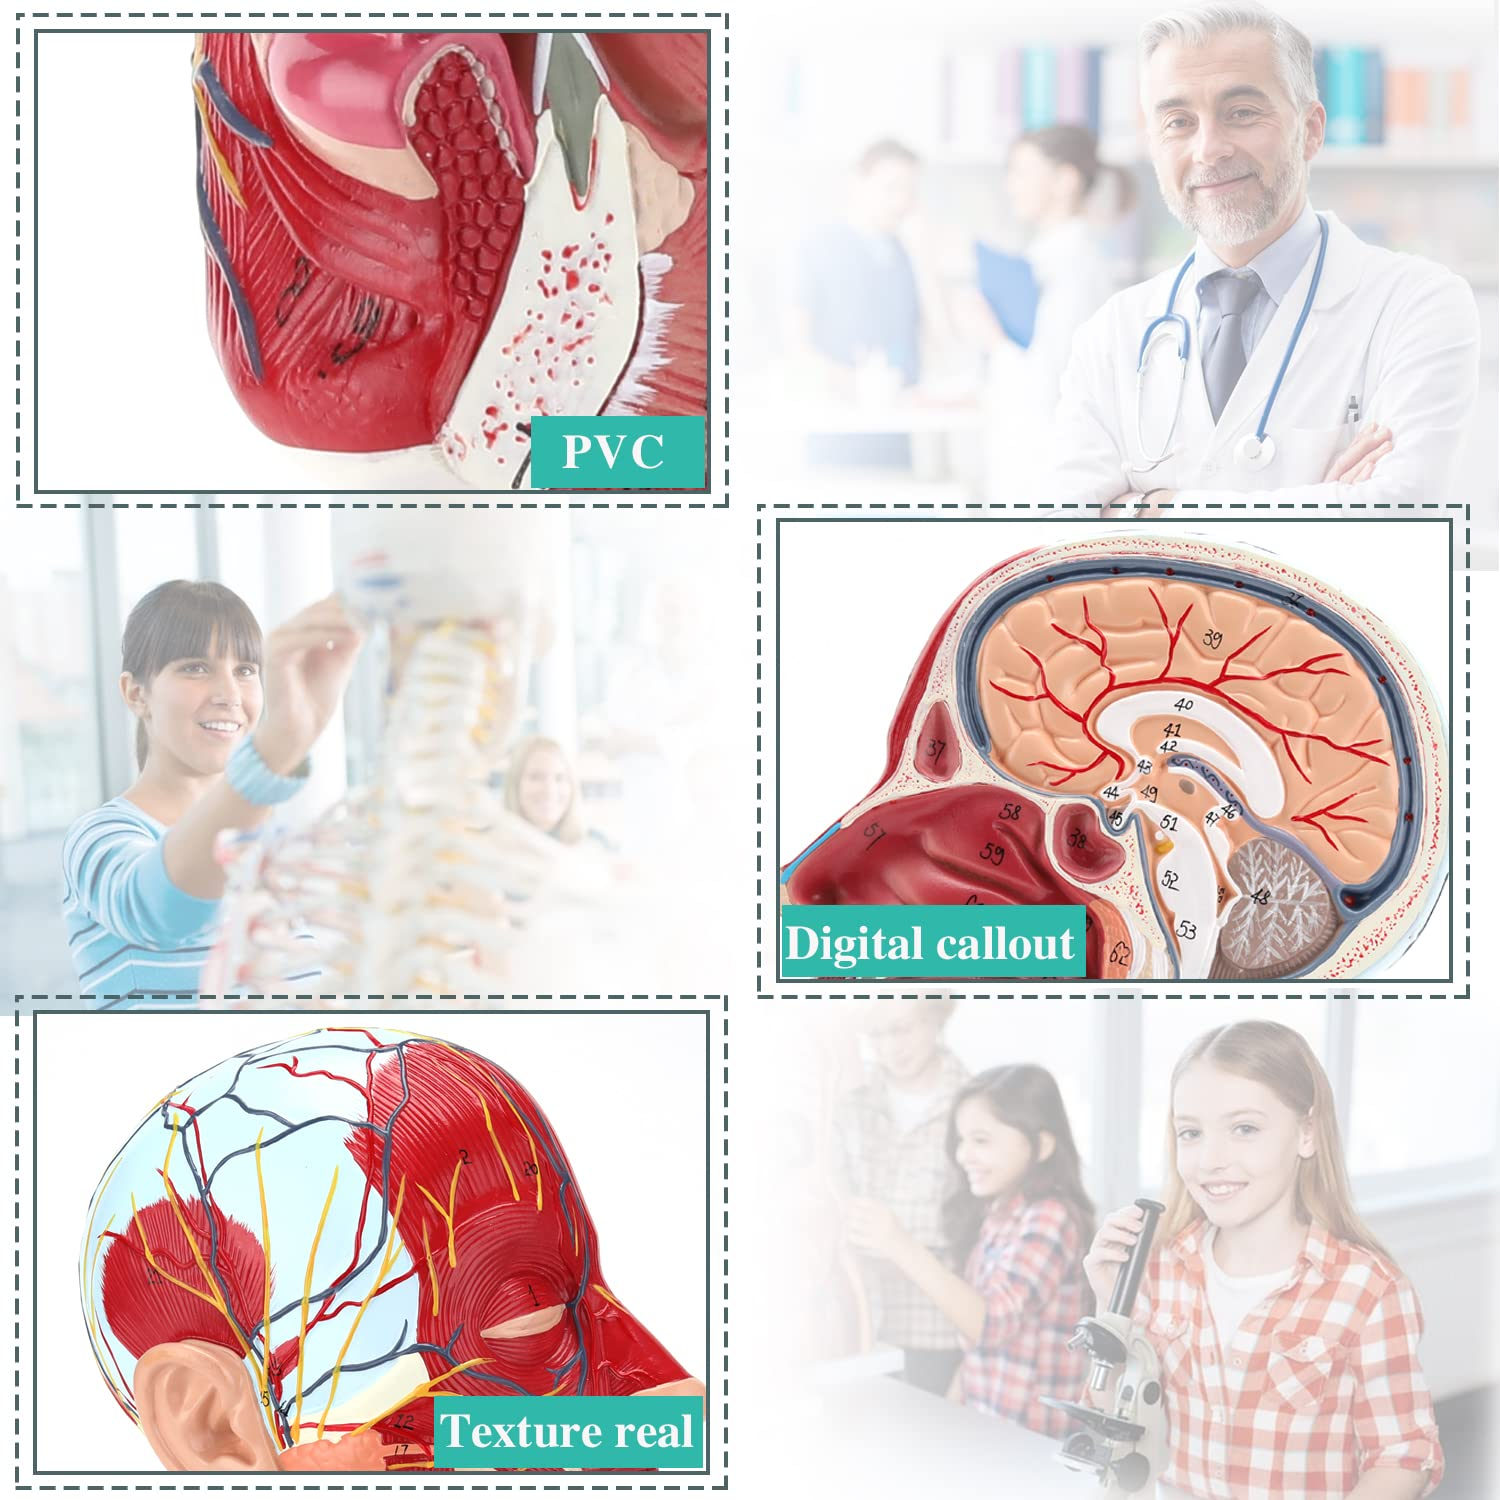

| ਸਮੱਗਰੀ | ਪੀਵੀਸੀ |

【ਉੱਚ ਕੁਆਲਟੀ】 ਦਿਮਾਗ ਦੇ ਸਰੀਰ ਵਿਗਿਆਨਕ ਮਾਡਲ, ਗੈਰ-ਜ਼ਹਿਰੀਲੇ ਵਾਤਾਵਰਣ ਦੇ ਅਨੁਕੂਲ ਪੀਵੀਸੀ ਸਮੱਗਰੀ ਦਾ ਬਣਿਆ, ਸਾਫ ਕਰਨਾ ਅਸਾਨ ਹੈ. ਸਰੀਰ-ਚਿੱਤਰ ਨੂੰ ਹੱਥ ਨਾਲ ਪੇਂਟ ਕੀਤਾ ਜਾਂਦਾ ਹੈ ਅਤੇ ਵੇਰਵੇ ਵੱਲ ਪੂਰਾ ਧਿਆਨ ਨਾਲ ਇਕੱਠਾ ਕੀਤਾ ਜਾਂਦਾ ਹੈ.

【ਸਤਹੀ ਨਿ ur ਰੋਵਸਕੂਲਰ ਮਾਸਪੇਸ਼ੀ ਦਾ ਮਾਡਲ】 ਉੱਚਿਤ ਵਿਸਥਾਰਪੂਰਕ, ਨੰਬਰ ਮਾਰਕ ਕੀਤੇ, ਕੰਬਦੇ ਕੰ the ੇ, ਨਾੜੀ ਅਤੇ ਗਰਦਨ ਦੇ ਅੰਦਰੂਨੀ structures ਾਂਚਿਆਂ ਦੀ ਸਮਝ ਨੂੰ ਡੂੰਘਾ ਕਰੋ. ਲਾਲ-ਧਮਣੀ, ਨੀਲੀ-ਨਾੜੀ, ਪੀਲੇ-ਨਸ.